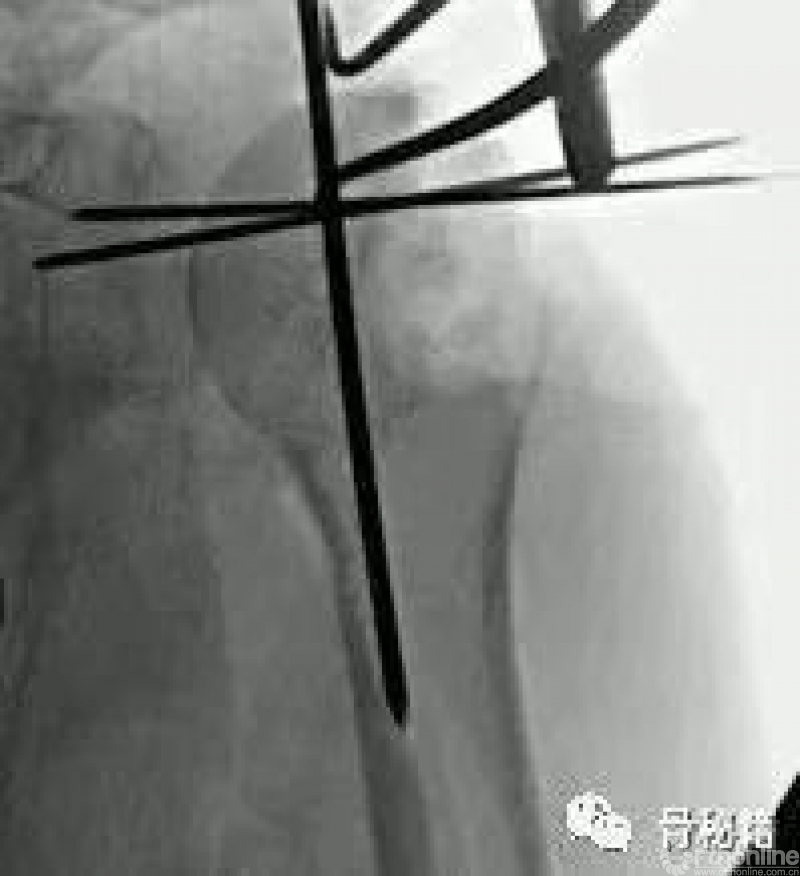

在复位好的基础上,植入合适的主钉导针

导针一旦植入,这个手术就完成了一半了

复位的关键就是将低头的肱骨头敲拨起来,外翻到合适的位置

可以应用摇杆技术等进行肱骨近端的复位,同时需要注意避让进针点的位置

也可以应用鞋拔子来进行翘拨复位,但是需要注意的问题是

外侧骨块必须是完整的,内侧一定要足够深入到头下的位置在骨量较好的地方进行翘拨